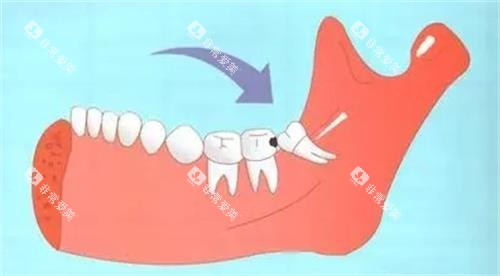

智齿的“脾气”各不相同:有的乖乖长在牙槽骨末端,有的却横着长、倒着长,甚至藏在骨头里“躲猫猫”。牙医们根据智齿的生长位置和拔除难度,将其分为三类:

阻生智齿:牙冠部分萌出或完全埋伏,被邻牙、骨头或软组织阻挡,需切开牙龈、去除部分骨质,价格在800-2000元/颗。

埋伏智齿:完全隐藏在颌骨内,需借助X光片定位,手术复杂度高,价格可能飙升至1500-4000元/颗。